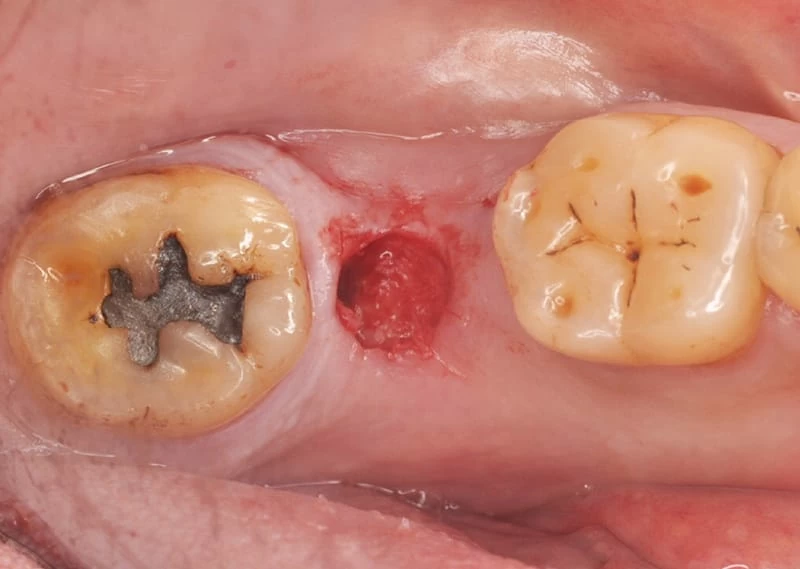

- 入人工牙根(進行植牙第一階段及第二階段)。<圖二~圖五>

植牙第一階段 <圖三>